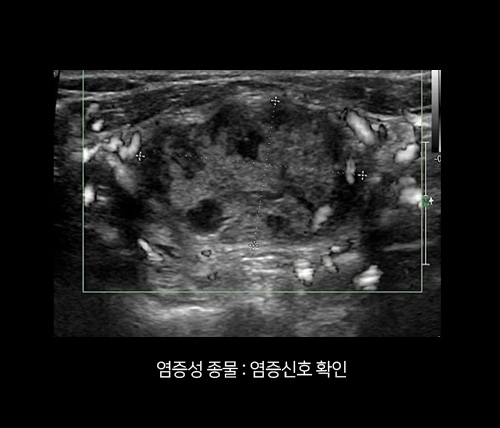

겉멍울은 ‘염증 신호’가 기준입니다.

피부 바로 아래에서 만져지는 멍울은 대부분 위험하지 않은 양성 종물인 경우가 많습니다.

다만 붉어짐, 열감, 통증, 고름 같은 분비물이 동반된다면

단순 혹이 아닌 염증이나 감염 가능성을 먼저 확인할 필요가 있습니다.

발적·열감·압통·분비물을

먼저 확인합니다.

초음파로 깊이/내용물/주변

침범 여부를 확인합니다.

염증 단계에 맞춰

치료 우선순위를 결정합니다.

치료는 “바로 제거”가 아니라 “염증을 먼저 잡고, 재발을 줄이는 제거”입니다.

짜거나 건드려 악화되기 전에 안전한 순서로 진행합니다.